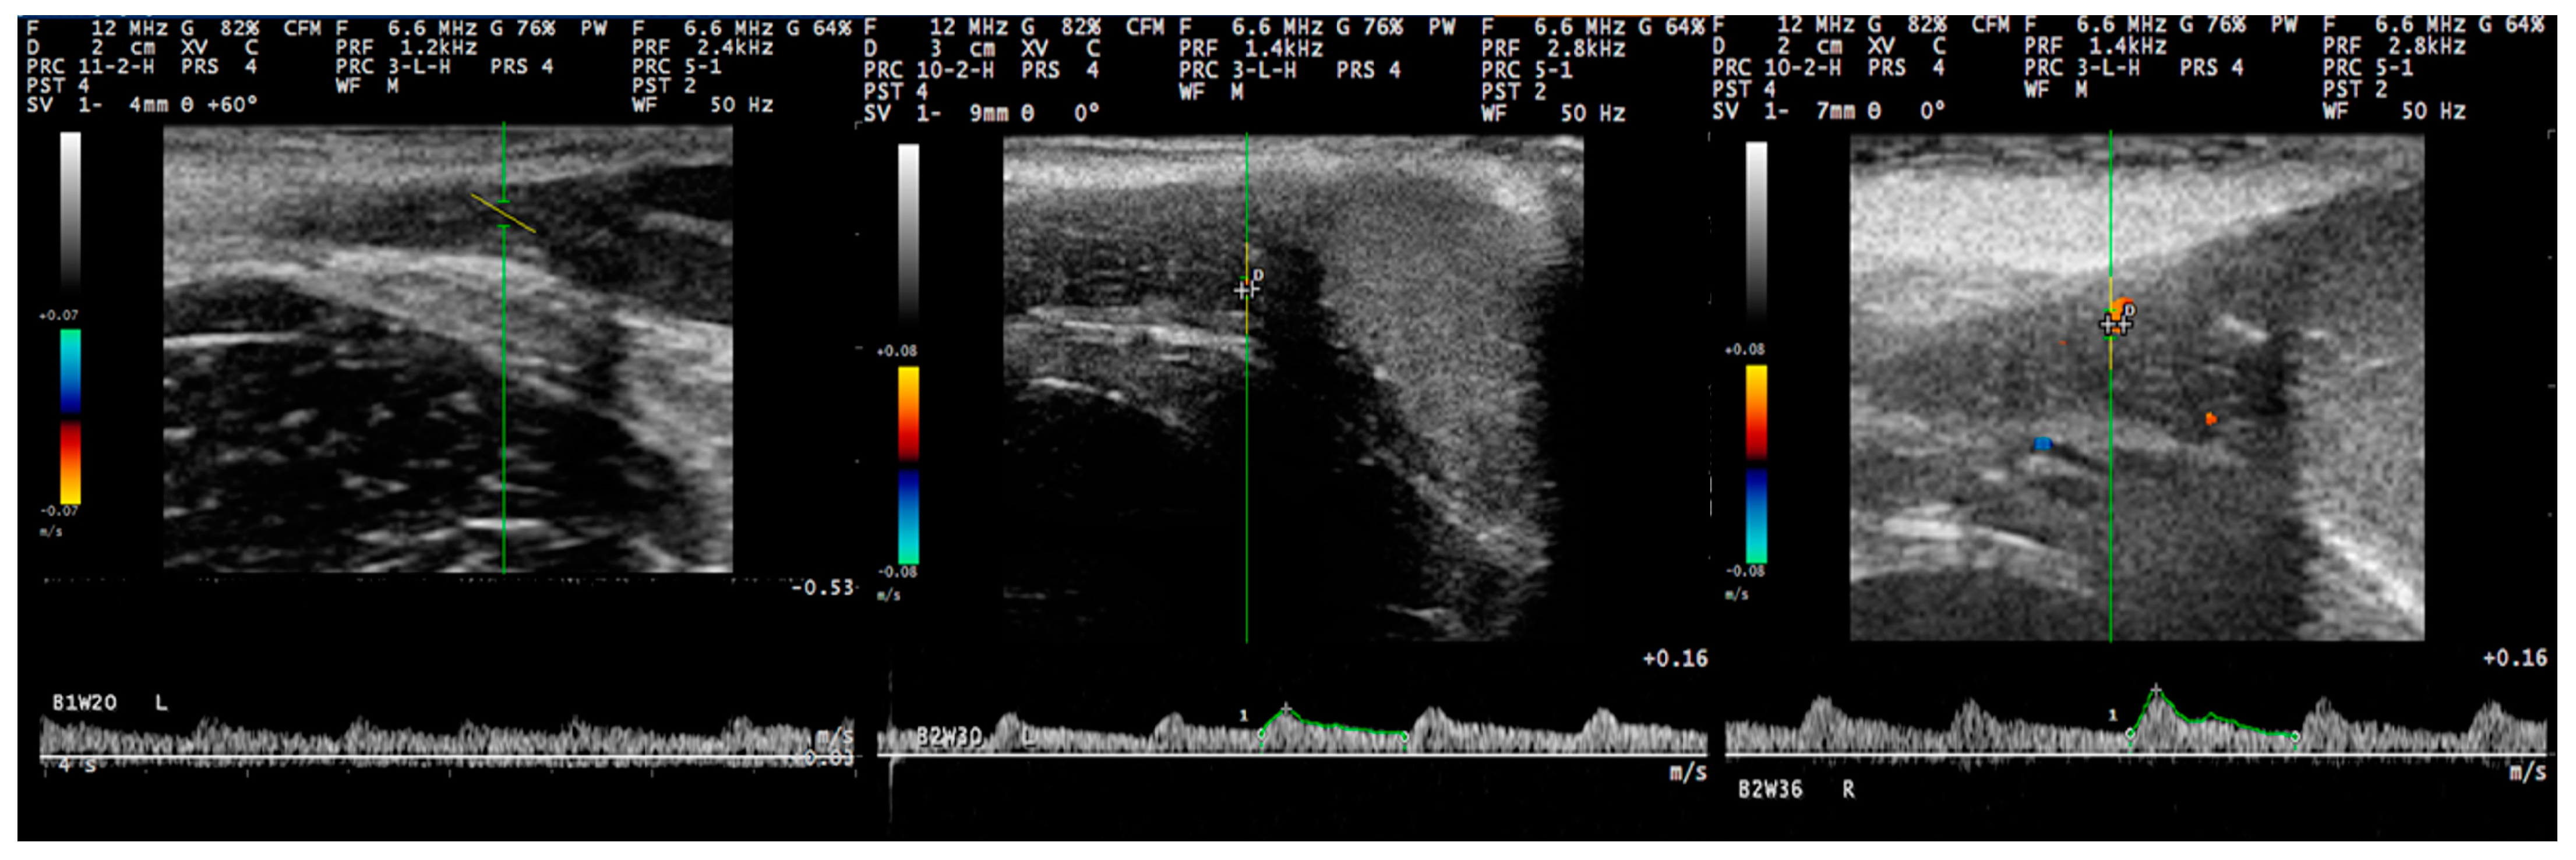

3.3. Pulsed-Wave Doppler

4.2. Differences in the Findings between the Regions of the Testis

4.4. Proposed Segments of the Artery and Haemodynamic Parameters for Doppler Evaluation